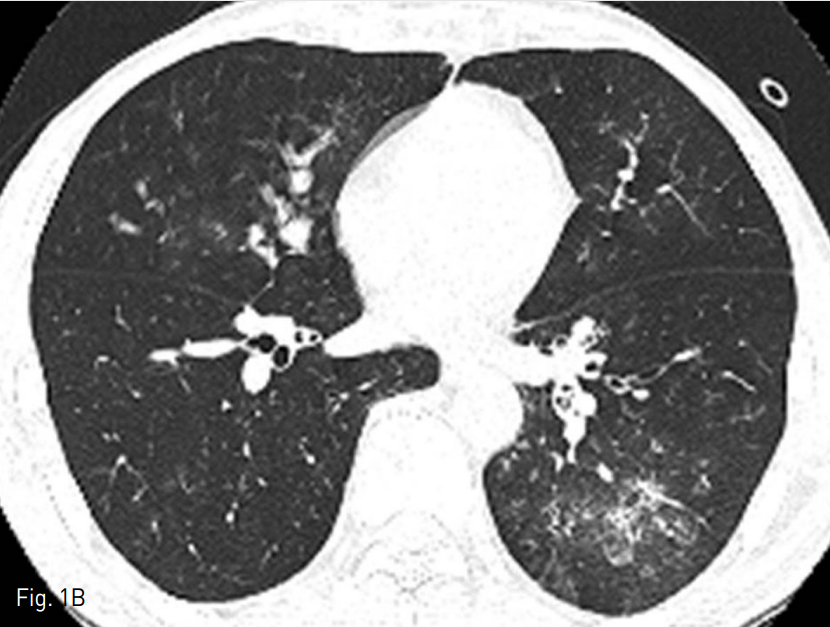

A. The post-contrast chest CT image shows diffuse wall thickening of the left lower bronchus (white arrow).

B. The high resolution chest CTimage reveals multifocal areas of ground glass opacity and consolidation in the right middle lobe and left low er lobe suggesting aspirated blood.